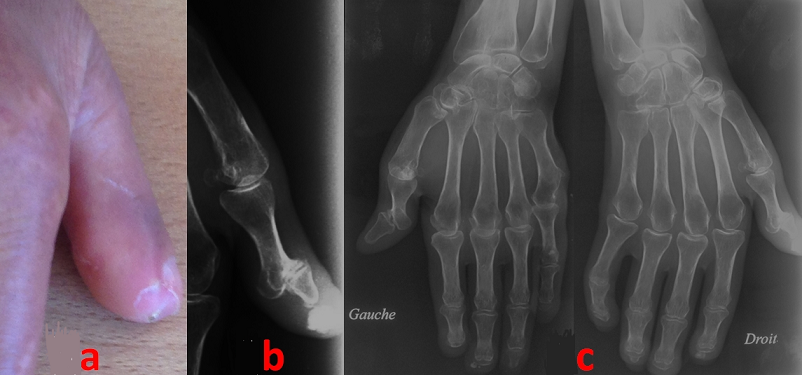

We report a case of 62-year-old Tunisian woman with a 10-year history of a CREST syndrome (systemic sclerosis meeting the criteria of the CREST syndrome of the 1980 American College of Rheumatology classification for raynaud phenomenon, esophageal dysmotility, sclerodactyly and telangiectasia). Her daughter is treated in neurology for myasthenia gravis. Our patient presents a 5-month history of increasing inflammatory right thumb pain concomitant with the discovery of a subcutaneous hard mass (A). Radiographs of her thumb showed a sub-cutaneous calcification (as another part of the CREST syndrome criteria) (B). X-rays of hands found an acro-osteolysis (C). In the CREST syndrome, the calcific deposits can be subclinical. But, when symptomatic, it becomes painful, tender and an inflammatory reaction can occur facing the calcinosis.